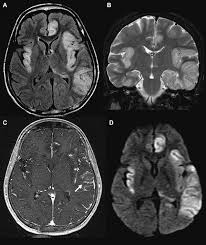

Pcr was repeated on the biopsy specimen and was positive for hsv. Limbic encephalitis, mca ischaemia, tumours, effects of seizures) hyperintense t2 signal in the medial temporal lobes, inferior frontal lobes and insula basal ganglia are usually spared Axial t2 prominent swelling, increase t2 signal involving the left temporal lobe and insular cortex. Multilocularis, and describes a spectrum of disease involving the spinal cord, the spine, or both. Mri is the diagnostic modality of choice abnormal in 90%; A brain biopsy was performed and the histology was consistent with encephalitis. Mri demonstrates extensive edema in the right temporal lobe with areas of intrinsic high t1 signal, in keeping with hemorrhage. For a general discussion, and for links to other system specific manifestations, please refer to the article on hydatid disease.

This patient went on to have hsv encephalitis proven on csf pcr.

The basal ganglia are usually spared. Mri is the diagnostic modality of choice abnormal in 90%; Hsv encephalitis | radiology case | radiopaedia.org. Axial t2 prominent swelling, increase t2 signal involving the left temporal lobe and insular cortex. For a general discussion, and for links to other system specific manifestations, please refer to the article on hydatid disease. Herpes simplex (hsv) encephalitis is the most common cause of fatal sporadic fulminant necrotizing viral encephalitis and has characteristic imaging findings. Herpes simplex virus (hsv) is a human herpesvirus that causes hsv encephalitis (hse), which is the commonest fatal sporadic encephalitis in humans. Hse may result from primary infection or reactivation from latency, and it frequently involves frontal or temporal lobes, as well as the brain stem. The differential diagnoses include limbic encephalitis (paraneoplastic), gliomatosis cerebri, and status epilepticus. A brain biopsy was performed and the histology was consistent with encephalitis. For a general discussion, and for links to other system specific manifestations, please refer to the article on hydatid disease. Cerebral malaria is a rare intracranial complication of a malarial infection. Bilateral temporal lobe t2 hyperintensity refers to hyperintense signal involving the temporal lobes on t2 weighted and flair imaging.

Two subtypes are recognised which differ in demographics, virus, and pattern of involvement. Terminology cerebritis is essentially the same as encephalitis except that it is used to denote brain par. There is also some cortical ribboning seen on dwi. Hsv encephalitis | radiology case | radiopaedia.org. Herpes simplex encephalitis (hse) is the most common form of viral sporadic encephalitis and, when left untreated, has a mortality rate of 70% (3, 22).

The changes spare the basal ganglia, a feature which is helpful in distinguishing an mca infarct with hemorrhagic transformation from herpes simplex encephalitis, the diagnosis in this case. Hse may result from primary infection or reactivation from latency, and it frequently involves frontal or temporal lobes, as well as the brain stem. Herpes simplex (hsv) encephalitis is the most common cause of fatal sporadic fulminant necrotizing viral encephalitis and has characteristic imaging findings. It is usually bilateral but asymmetrical. The differential diagnoses include limbic encephalitis (paraneoplastic), gliomatosis cerebri, and status epilepticus. Two subtypes are recognized which differ in demographics, virus, and pattern of involvement. Given the history of fever and seizures coupled with the mri findings of bilateral mesial temporal lobe changes, herpes encephalitis requires clinical consideration. Spinal hydatid disease is an uncommon manifestation of hydatid disease, caused by the larval stage of echinococcus granulosus, or less commonly e. Multilocularis.the larval stage is the cause of hydatid disease in humans 1. The differential diagnoses include limbic encephalitis (paraneoplastic), gliomatosis cerebri, and status epilepticus. Herpes simplex encephalitis (hse) is the most common form of viral sporadic encephalitis and, when left untreated, has a mortality rate of 70% (3, 22). This patient went on to have hsv encephalitis proven on csf pcr. Bilateral temporal lobe t2 hyperintensity refers to hyperintense signal involving the temporal lobes on t2 weighted and flair imaging.